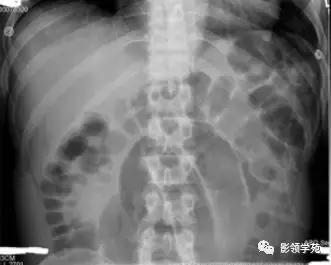

X线腹部平片检查可发现肠腔充气,并有液气平面、闭襻肠管影。上消化道泛影葡胺造影和小肠镜检查可观察近端小肠梗阻,但在怀疑有结肠梗阻的病人禁用消化道造影。腹部术后出现早期肠梗阻者,应注意是否存在低钾血症、术后早期炎性肠梗阻、术后胃肠无力症、术后肠麻痹、术后肠系膜血管栓塞或血栓形成等。